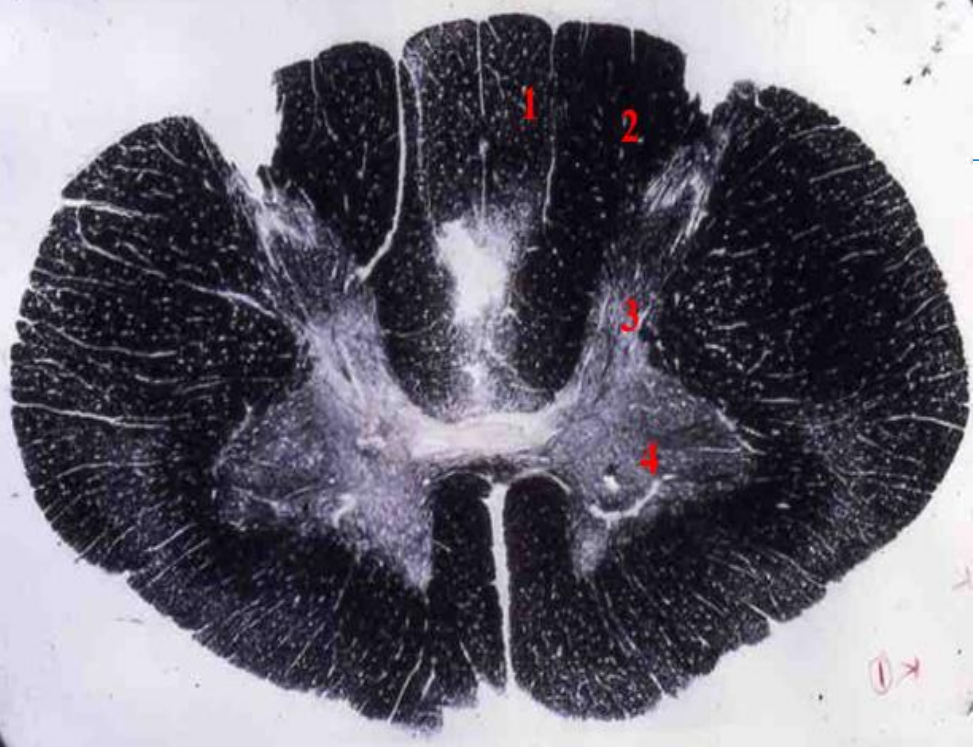

5

thoracic cord

- Fibre tracts are larger

- Grey matter is scanty as no limb plexuses

How well did you know this?

6

Q

1

A

fasciculus gracilis